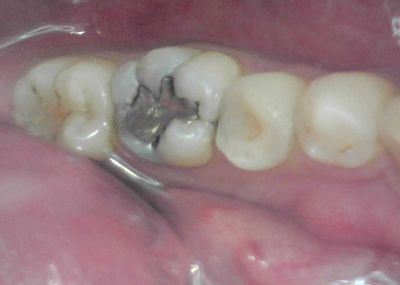

●なるべく歯の神経は残してあげたいとは思っている。

のだけれども、まあ、僕も結構色々散々やってはきたんだけれども、

結局腐ってる(細菌感染してる)神経には何してもダメという当たり前の結論に

到達しております。

神経がこんな感じに腐ってたらもう、取るしか方法ないですわな。

逆に言えば、腐ってさえいなければ助けられるかもということではあるのですが、

感染してるかどうかって外からじゃあんましわかんないんで、開けて中見るしかない。

経験上、何もしなくてもズキズキ傷んでた場合はほぼダメです。

冷たいのがしみるかな?くらいだと助かることは多いです。